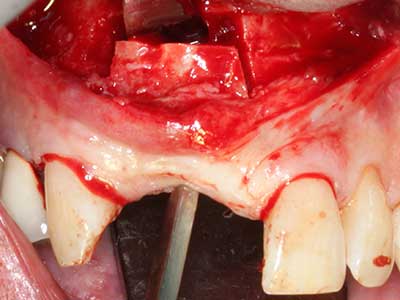

La piezochirurgia presenta altri vantaggi per quanto riguarda la raccolta di blocchi ossei. Oltre all'elevata precisione dell'osteotomia appena descritta, l'utilizzo di puntine per sega molto sottili permette di minimizzare in maniera significativa la perdita di materiale. È molto probabile che si verifichi una maggiore perdita di materiale durante la raccolta utilizzando puntine di strumenti più spessi, in particolare delle frese Lindemann (Lakshmiganthan, Gokulanathan et al. 2012). La separazione basale, necessaria in particolare per i trapianti di blocchi nella zona retromolare, viene semplificata grazie a seghe specificatamente progettate di forma rettangolare; di conseguenza la piezochirurgia è considerata una procedura precisa, semplice e sicura per la raccolta di blocchi di osso nella zona retromolare (Happe 2007) (figg. 1-12).

Indicazione: incisione ossea

Il tessuto osseo non è semplicemente una struttura minerale, ma contiene anche una percentuale significativa di fibre di collagene. Ciò significa che non possiede solo una buona forza di compressione, ma anche un certo livello di flessibilità che è possibile sfruttare durante l'esecuzione degli accrescimenti di osso. Nella procedura di espansione classica con incisione ossea, la cresta alveolare atrofizzata viene incisa longitudinalmente ed espansa con cautela dopo aver raggiunto una profondità di osteotomia adeguata (figg. 13-16), idealmente senza una sostanziale rimozione del periostio (Brugnami, Caiazzo et al. 2014, Stricker, Fleiner et al. 2014). I sistemi a piastra e vite con distanza di espansione incrementale si sono dimostrati efficaci nella separazione delle due lamelle ossee restando al di sotto della soglia di frattura. In generale, sono richieste larghezze dell'osso residuo di almeno 3-4 mm (Chiapasco, Zaniboni et al. 2006) per garantire un'adeguata flessibilità e una copertura sufficiente dell'osso per gli impianti futuri. Se necessario, un'osteotomia di rilascio verticale su uno o più lati può migliorare la flessibilità. Una combinazione con ulteriori tecniche di accrescimento, in particolare dal lato buccale, è stata descritta come un'alternativa alla tecnica classica.

La procedura di incisione è particolarmente atraumatica e non comporta una perdita significativa di dimensione durante l'utilizzo delle seghe piezoelettriche, così come non si notano differenze rilevanti tra impianti in mandibole incise e impianti in una cresta alveolare senza deficit osseo (Chiapasco, Zaniboni et al. 2006, Danza, Guidi et al. 2009). Una sufficiente irrigazione continua è essenziale, tuttavia, in particolare con incisione profonda e localmente ristretta, per prevenire la sollecitazione termica nelle regioni apicali dell'osteotomia.